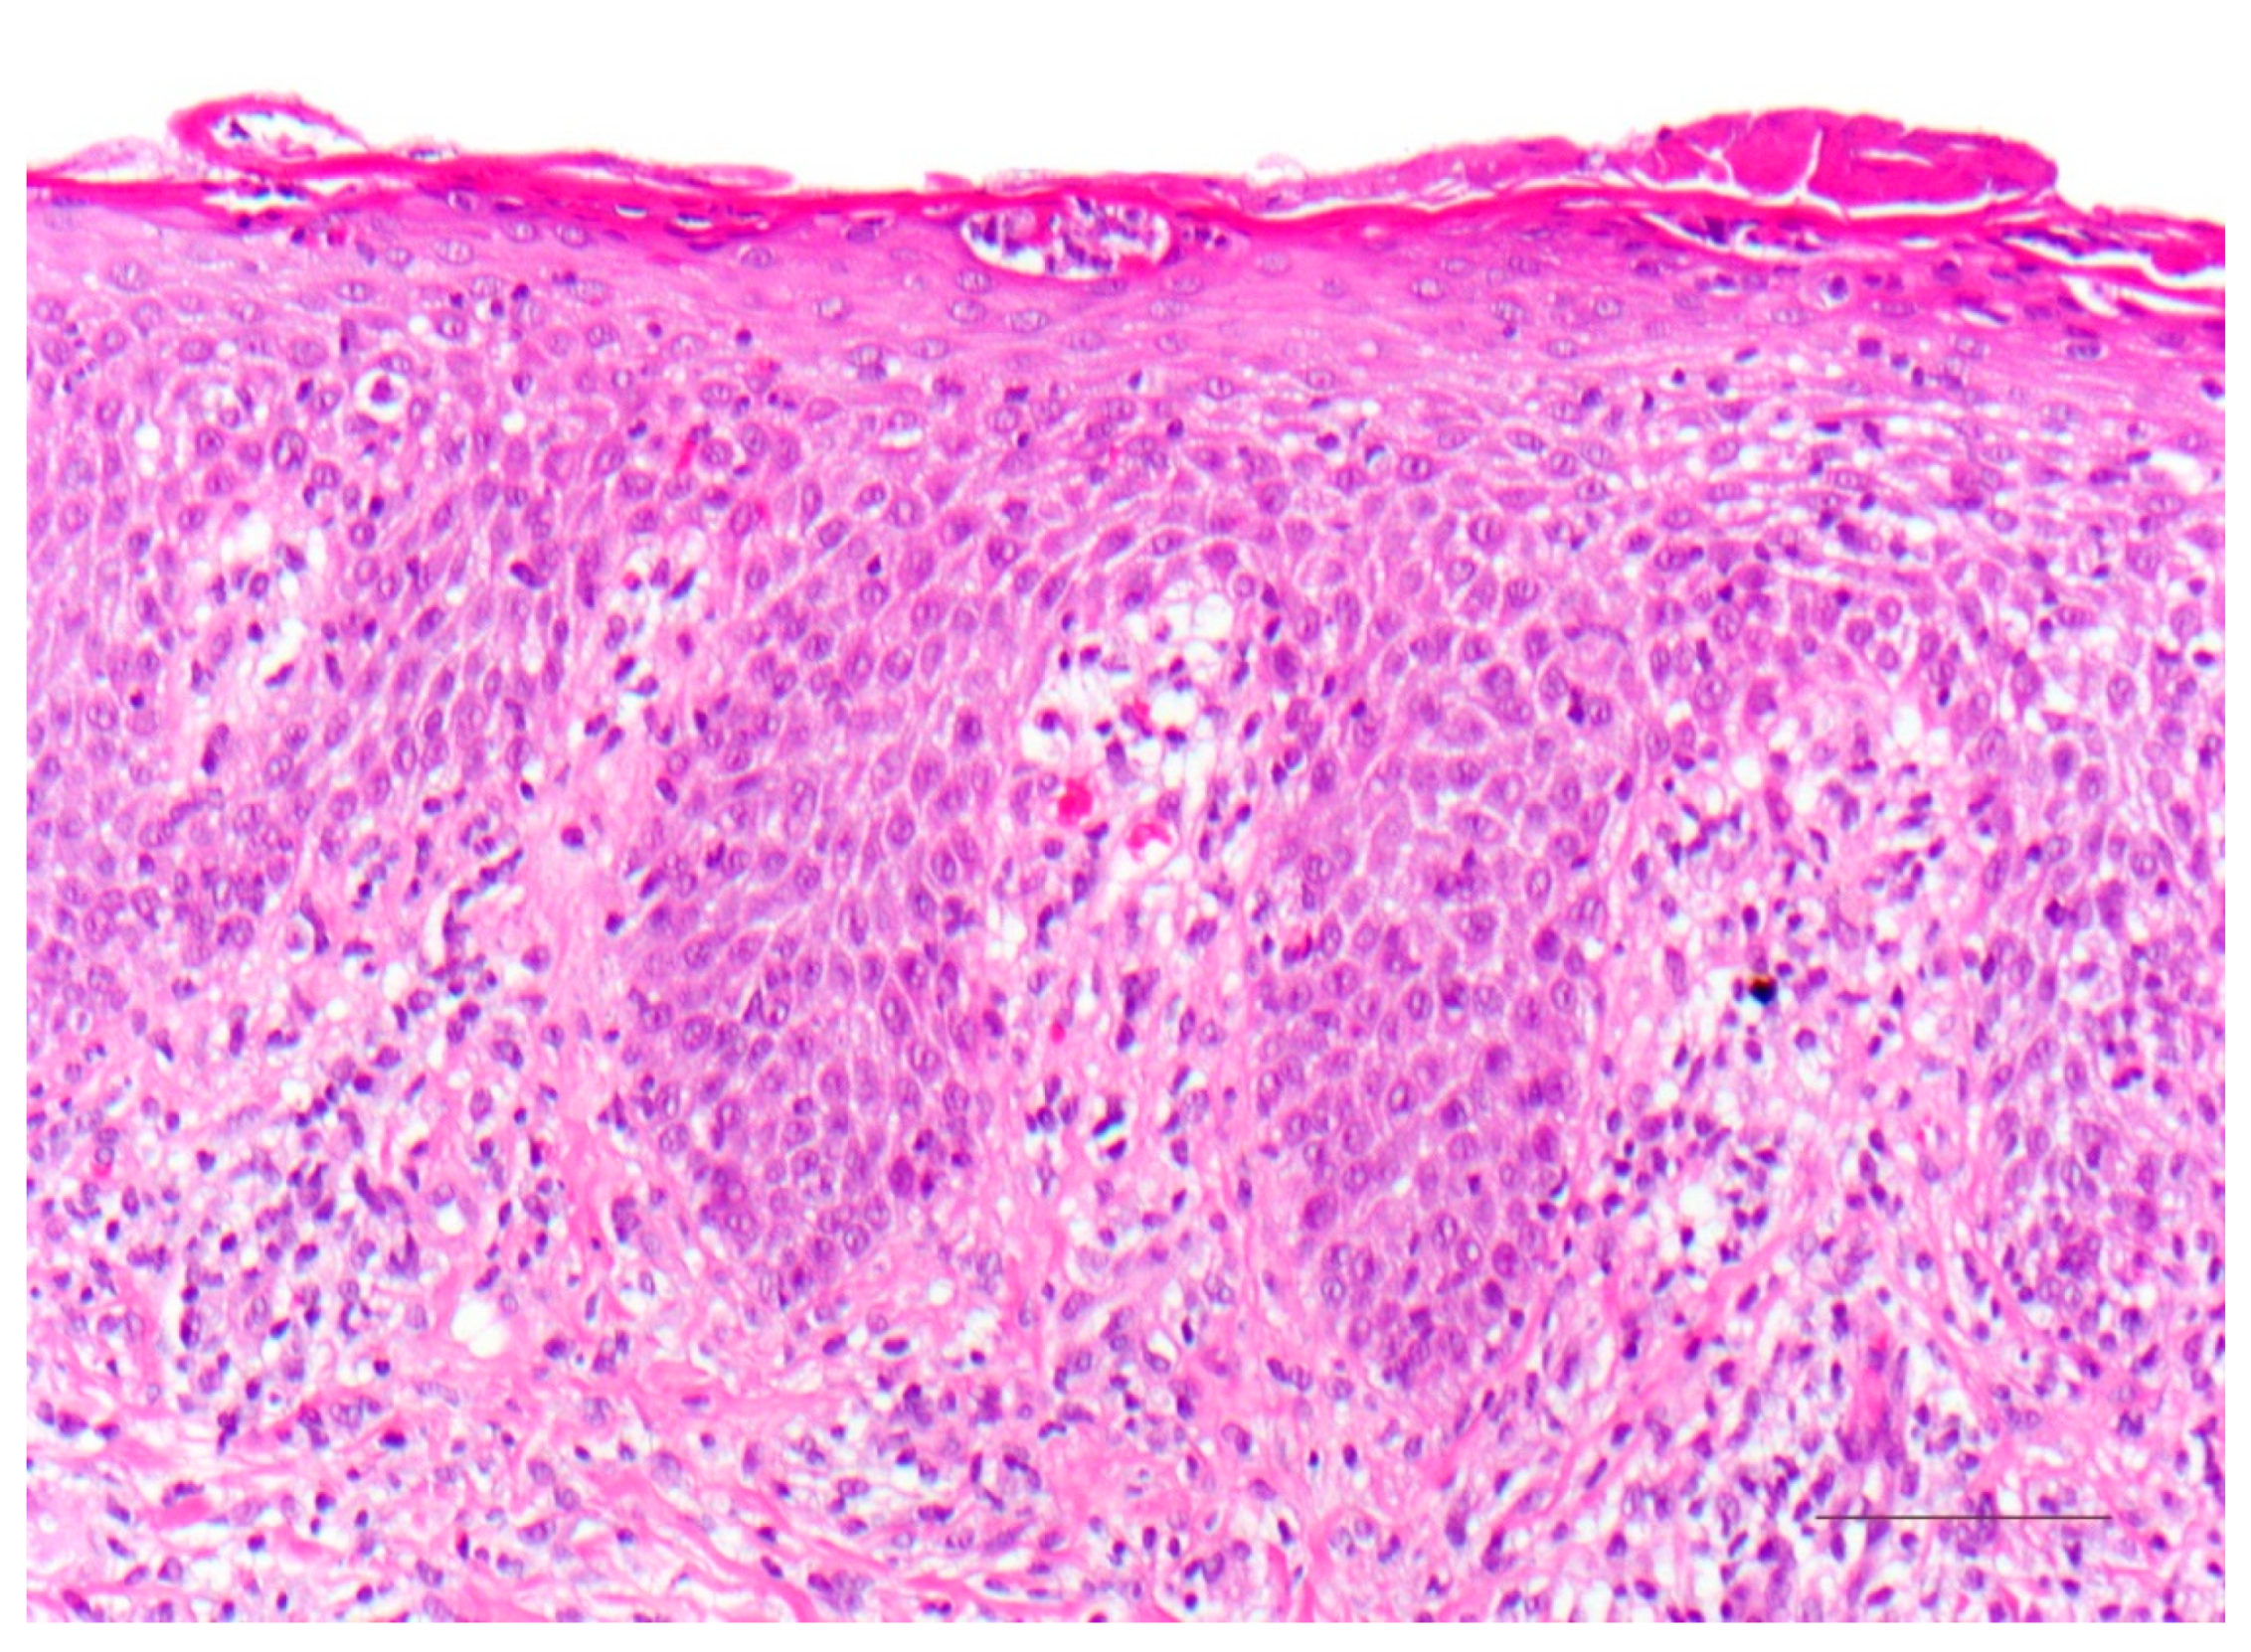

5. Keratinopathic Ichthyosis

5.1. Histology